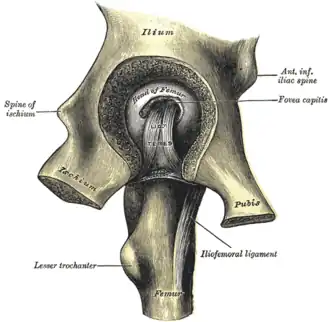

Left hip-joint, opened by removing the floor of the acetabulum from within the pelvis. | |